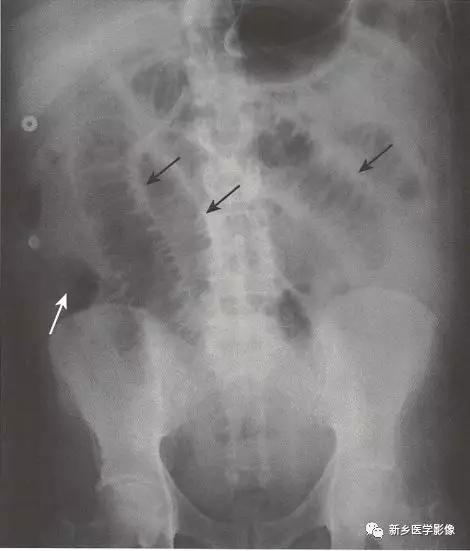

传统X线平片上,梗阻点近端可见多个扩张的小肠肠襻(>2.5cm)。

当肠 腔开始扩张,小肠肠襻逐一 堆积,形成阶梯状外观,一般由左上腹开始,随着疾病进展逐步向右下腹(黑色实线箭头)发展,具体范围及程度取决于小肠梗阻点有多远。

一般来说,若是近端小肠梗阻(例如近端空肠),则扩张的小肠肠襻数量较少;若是远端小肠梗阻(例如回盲瓣处),则扩张的小肠肠襻数量较多。

在直立位或侧卧位片上,在梗阻近端小肠通常可见多个气-液平面。

如果时间足够长,梗阻远端的肠道内容物可完全排出,则在结肠尤其是直肠内只有很少或完全见不到气体影。

在机械性小肠梗阻中,相对于塌陷的大肠,小肠往往表现为不成比例的显著扩张。